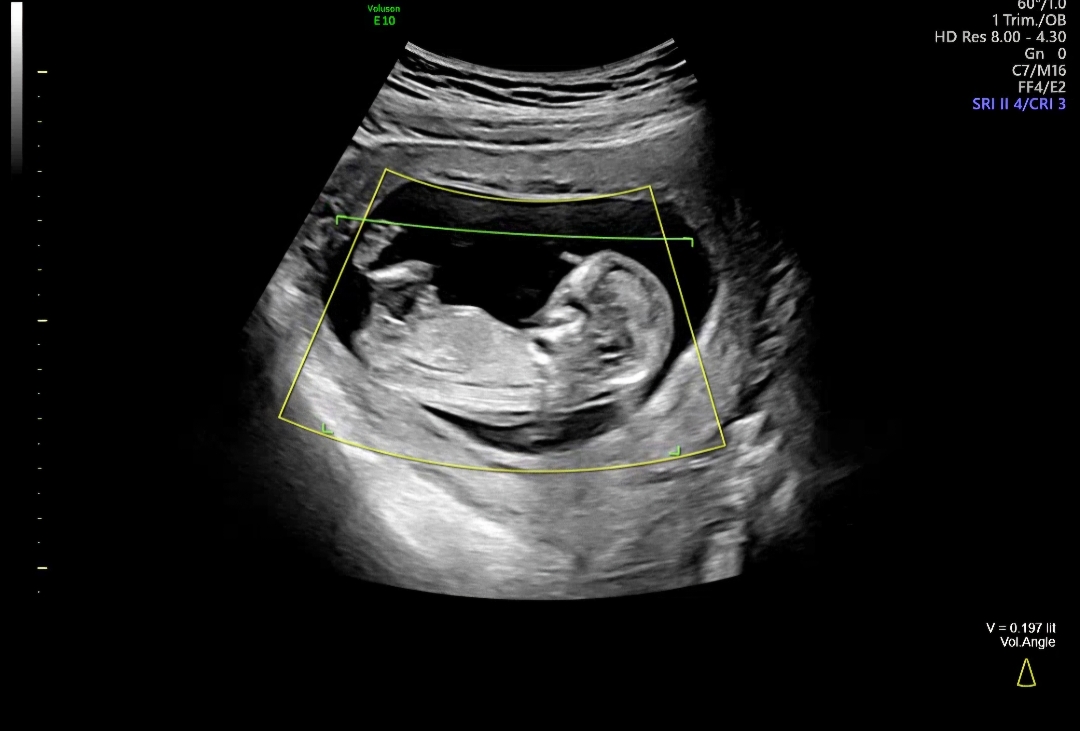

12주 각도법 좀 봐주세요ㅎㅎ

12주가 되서 각도법 성별 궁금해서요ㅎㅎ 한번 좀 부탁드립니당!

아들같아요

저랑 비슷한거같은데 초음파샘이 아들확률있다셨으니 아들한표요!!!